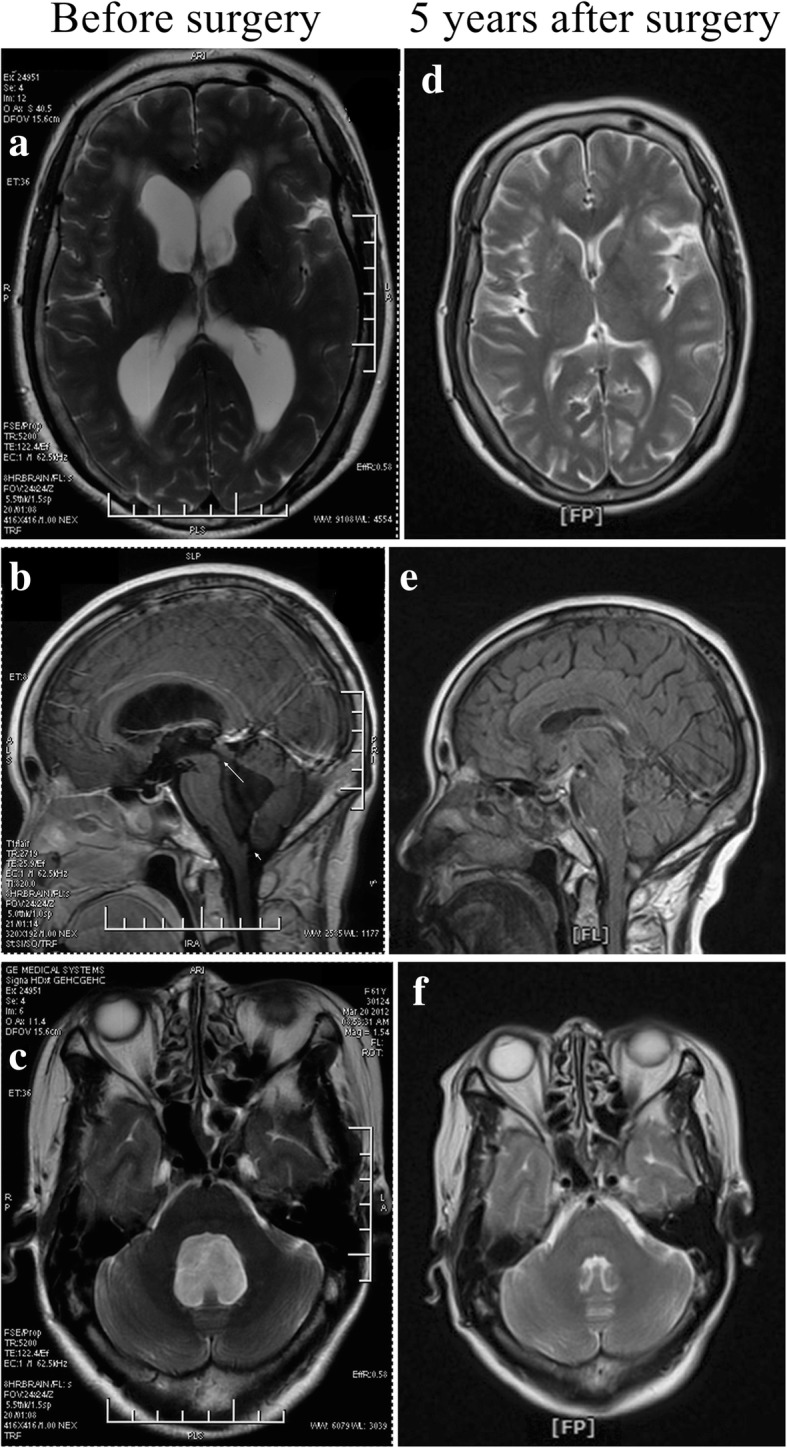

A 51-year-old Han Chinese woman was admitted with a 1-year history of headache and dizziness. She had received no past interventions. She had no medical, family, or psychosocial history. Clinical examination showed the Romberg’s sign. Magnetic resonance imaging (MRI) demonstrated hydrocephalus with a disproportionately large fourth ventricle (Fig. 1a–c). She underwent a VP shunt (PS Medical programmable valve set at 1.0, which was equivalent to the opening pressure of 50–70 cmH2O in the upright position; Medtronic, Minneapolis, MN, USA) of the right lateral ventricle and had an uneventful postoperative course. Her symptoms were relieved totally. Five years later, MRI still showed a normal ventricular system (Fig. 1d–f). The parameter of the opening pressure of the programmable valve has never been adjusted because she has never had any discomfort.

Fig. 1.

Preoperative (a–c) and postoperative (d–f) magnetic resonance imaging of a typical disproportionately large communicating fourth ventricle in patient 1. → Preoperative dilated aqueduct

Both of our patients were DLCFV. Patient 1 presented with a tetraventricular hydrocephalus that returned to normal after shunting the lateral ventricle, which indicated that the aqueduct had been patent or reopened due to the disappearance of the pressure gradient between the supratentorial and infratentorial compartments. Patient 2 presented with not only tetraventricular hydrocephalus but also syringomyelia and crowded posterior fossa, which fulfilled the concept of isolated rhombencephalic ventricle or holoneural canal dilatation proposed by Qi and Abbott [14]. The dramatic regression of patient 2’s clinical and radiological signs shortly after posterior fossa decompression proved the functional obstruction of the outlets, which was in accord with the definition of DLCFV and prompted the role of the crowded posterior fossa in the pathophysiology of DLCFV.

Patient 1 was a typical case of DLCFV without crowded posterior cranial fossa or other abnormality. She was cured successfully with a supratentorial VP shunt. However, the decision-making of the treatment strategy of patient 2 has been a puzzle. He had a crowded posterior fossa and cervical syringomyelia, which could have led to the obstruction of the outflow of CSF from the fourth ventricle. Because it has been proved that the DLCFV is not always responsive to VP shunt and the supratentorial CSF shunt, especially the low-pressure shunt system would increase the risk of upward herniation of the cerebellar tissue. Thus, in view of the obviously crowded posterior fossa and the syringomyelia, the posterior fossa decompression with duraplasty turned into the option of initial management. Although the major cerebellar ptosis could not be considered as a good imaging outcome, patient 2 obtained a good clinical outcome. The effectiveness of posterior fossa decompression to treat postshunt IFV has been reported [3]. Our cases suggested that posterior fossa decompression could be a choice for the initial management of the DLCFV coexisting with crowded posterior cranial fossa or syringomyelia.